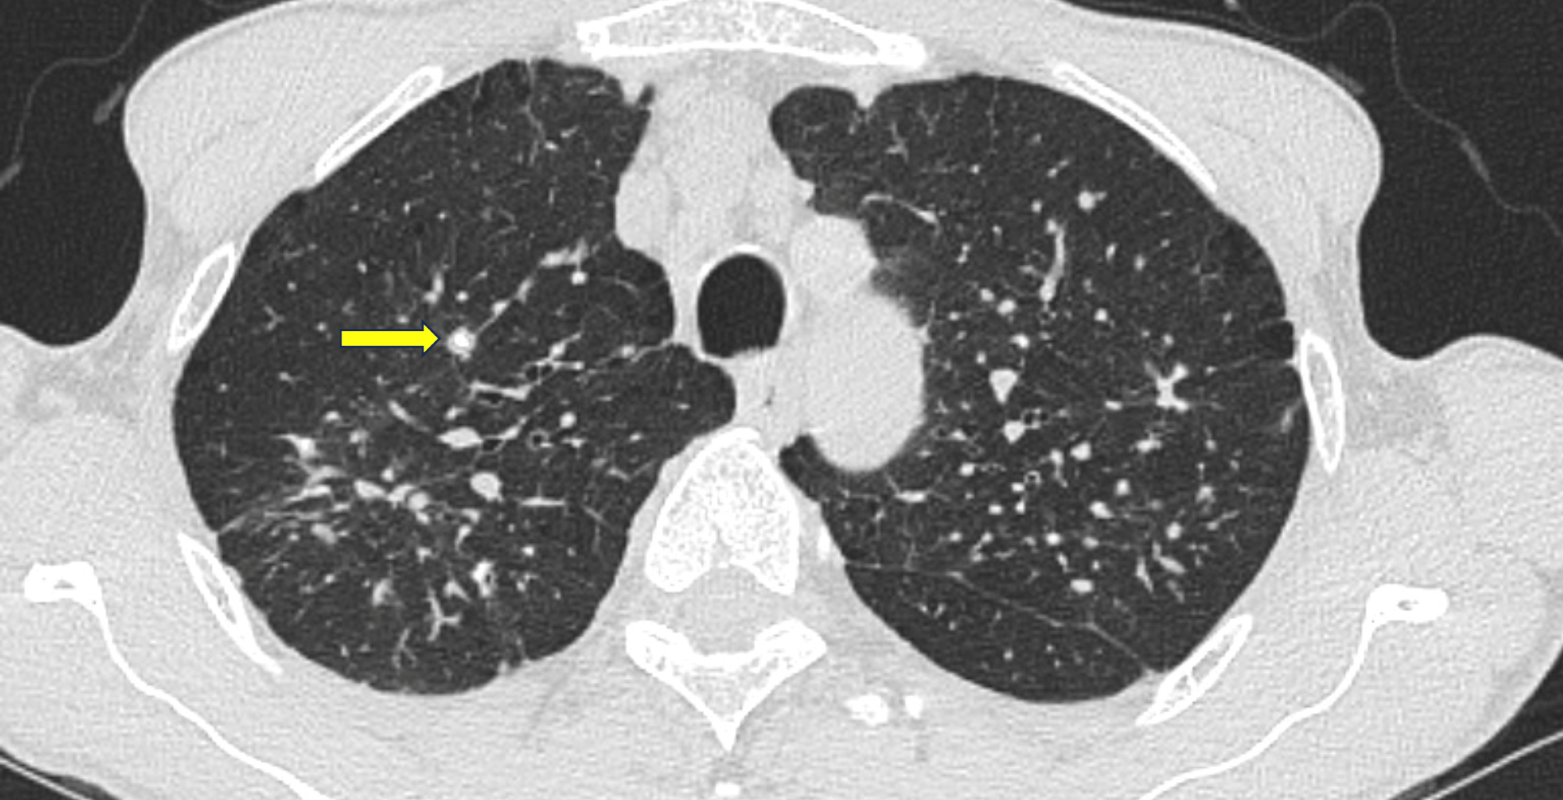

肺部高分辨率计算机断层扫描(HRCT)显示多个边界清晰的肺结节

,肺尖和周围易受累,肺底相对正常(图1和2)。结节的直径从约几毫米到一厘米不等,并显示散在钙化(图3)。在上叶这些结节显示出融合趋势;没有空洞形成。也有轻度肺气肿

以及弥漫性支气管壁增厚。患者最终诊断为Caplan综合征。

图3 轴位CT显示肺结节伴有散在病灶内钙化(箭头)